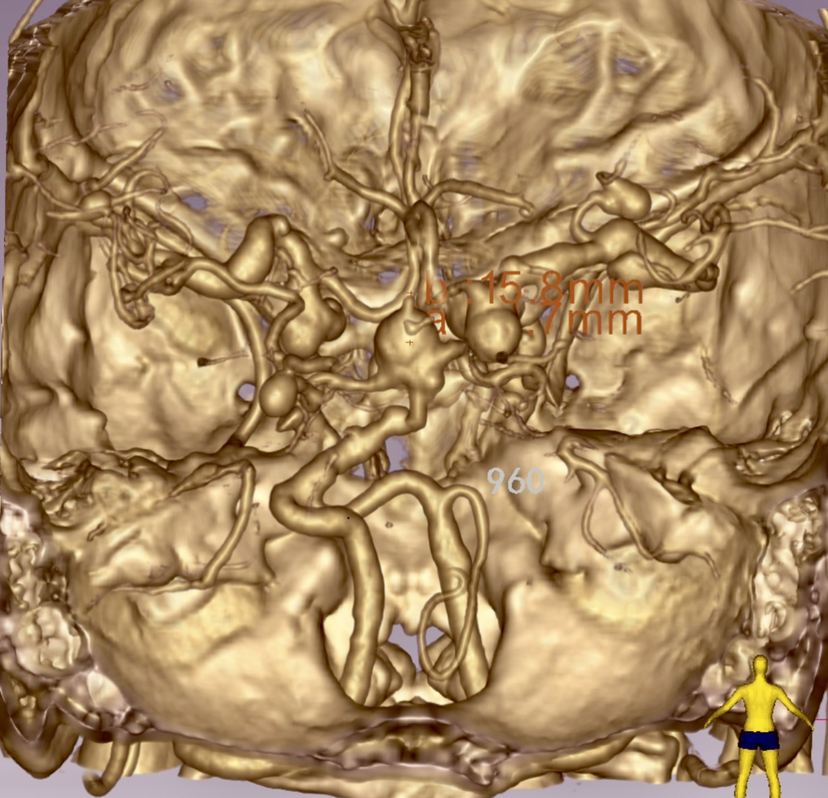

DSA检查发现颅内共12枚形态各异的动脉瘤,其中基底动脉瘤形态不规则,大小约15*13mm,瘤颈部累及双侧大脑后动脉P1段,双侧后交通动脉和前交通动脉不显示,瘤顶部有子囊发出。